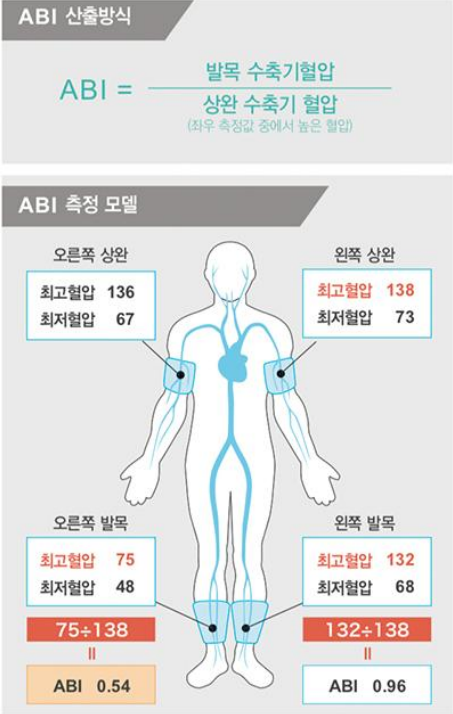

혈관 경직도 검사는 무엇입니까?팔과 다리의 혈압과 맥박의 파동을 분석하여 전신의 동맥은 얼마나 굳어 있는 것입니까? 혹시 막힌 데는 없나? 검사하겠습니다.

① ABI 점수(ankelbrachealin dex) : 손발의 혈압 차이가 얼마나 나는지 평가합니다. 팔 혈압은 높지만, 다리의 혈압은 너무 낮으면 다리의 혈관이 막힌 것이 아닐까요? 0.9보다 낮은 점수가 나오면 말초혈관질환이 의심됩니다.ABI 점수분석 1.0 1.0 1.0 정상 0.9-0.99 말초혈관질환? borderline/혈관내피세포의 이상발생 시사 0.7-0.89 말초혈관질환 있음 mild 0.5-0.69 말초혈관질환 있음 moderate < 0.5 심각한 말초혈관질환, 괴사발생가능성이 높은 점수가 낮을수록 혈관상태가 나쁠 수 있습니다.